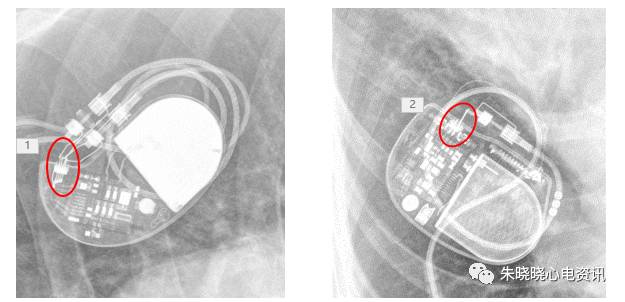

如圣犹达起搏器典型的接线方式是独有的一个长方形线圈(图8)

图8 圣犹达起搏器

波士顿科学起搏器部分接线为数条导线并排,可联想为蜈蚣帮助记忆(图9)

图9 波士顿科学起搏器

另有部分起搏器接线方式像长梯(图10)

图10 波士顿科学起搏器